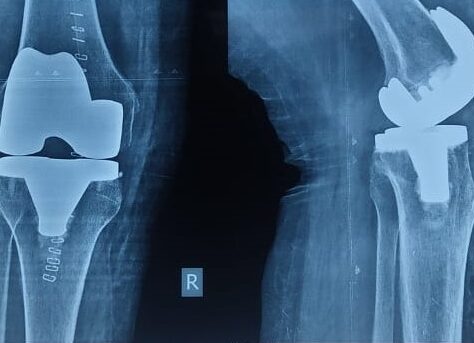

Total knee replacement, also called knee arthroplasty, is a surgical procedure where damaged cartilage and bone in the knee joint are removed and replaced with artificial components made from metal alloys and high-grade plastics. The surgery aims to restore function and reduce pain in severely diseased knee joints.

- Component Placement: Metal components are attached to the bone surfaces using cement or press-fit technique. A plastic spacer is inserted between the metal components to create a smooth gliding surface.

Types of Knee Replacement

Total Knee Replacement: All three compartments of the knee joint are replaced. This is the most common type performed at facilities like Dr. Chandan’s Joint Clinic.

Revision Knee Replacement: A second surgery performed when a previous replacement wears out or fails.